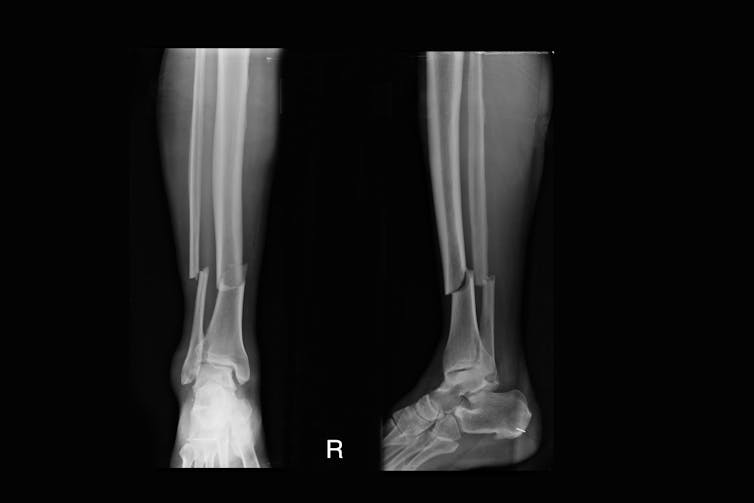

Another major problem is that around 5-10% of fractures don’t heal properly. Common causes are fractures that are difficult to hold together, or low blood flow to the area. Some important risk factors include the severity of the fracture, smoking, old age, obesity and diabetes. The bones in the hand, the tibia and fibula (both in the leg) and the femur (thigh bone) are also more prone to improper healing.

Here is where a bit of exercise can help. A study looking at 166 surgically treated tibia fractures discovered that early weight-bearing exercise was linked with faster healing – even in participants who had fractures that weren’t healing properly.

Healing was defined as the person’s ability to bear full weight with no pain, and with x-rays showing the fracture had united or mended. On the other hand, a small study investigating what would happen if people didn’t do weight-bearing exercises six weeks after surgery showed participants had significant bone loss.